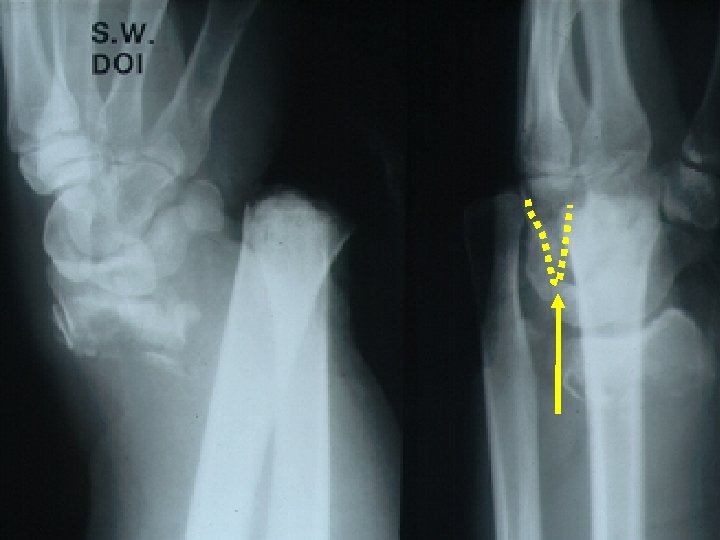

Заключительный результат Слишком поздно! День травмы 6 недель